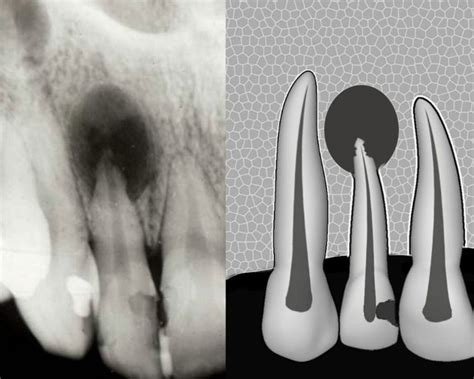

Quiste Radicular

Son quistes que derivan de los restos epiteliales del ligamento periodontal (restos de Malassez) que inician su actividad al ser estimulados por un proceso inflamatorio, generalmente después de una necrosis pulpar. Se desarrollan cuando se produce inflamación pulpar en la región periapical o lateral radiculares, o bien tras la formación de un granuloma apical o lateral.

Cuando en un granuloma existen restos epiteliales de Malassez y estos son estimulados por un proceso inflamatorio, se inicia su proliferación hasta lograr delimitar una cavidad quística epitelial. Es el quiste más frecuente de los maxilares, representan más del 50%. Se desarrollan sobre todo en la dentición permanente, en los dientes temporales son muy infrecuentes, ya que suponen solamente del 0,5 al 3,3% del total de los quistes radiculares.